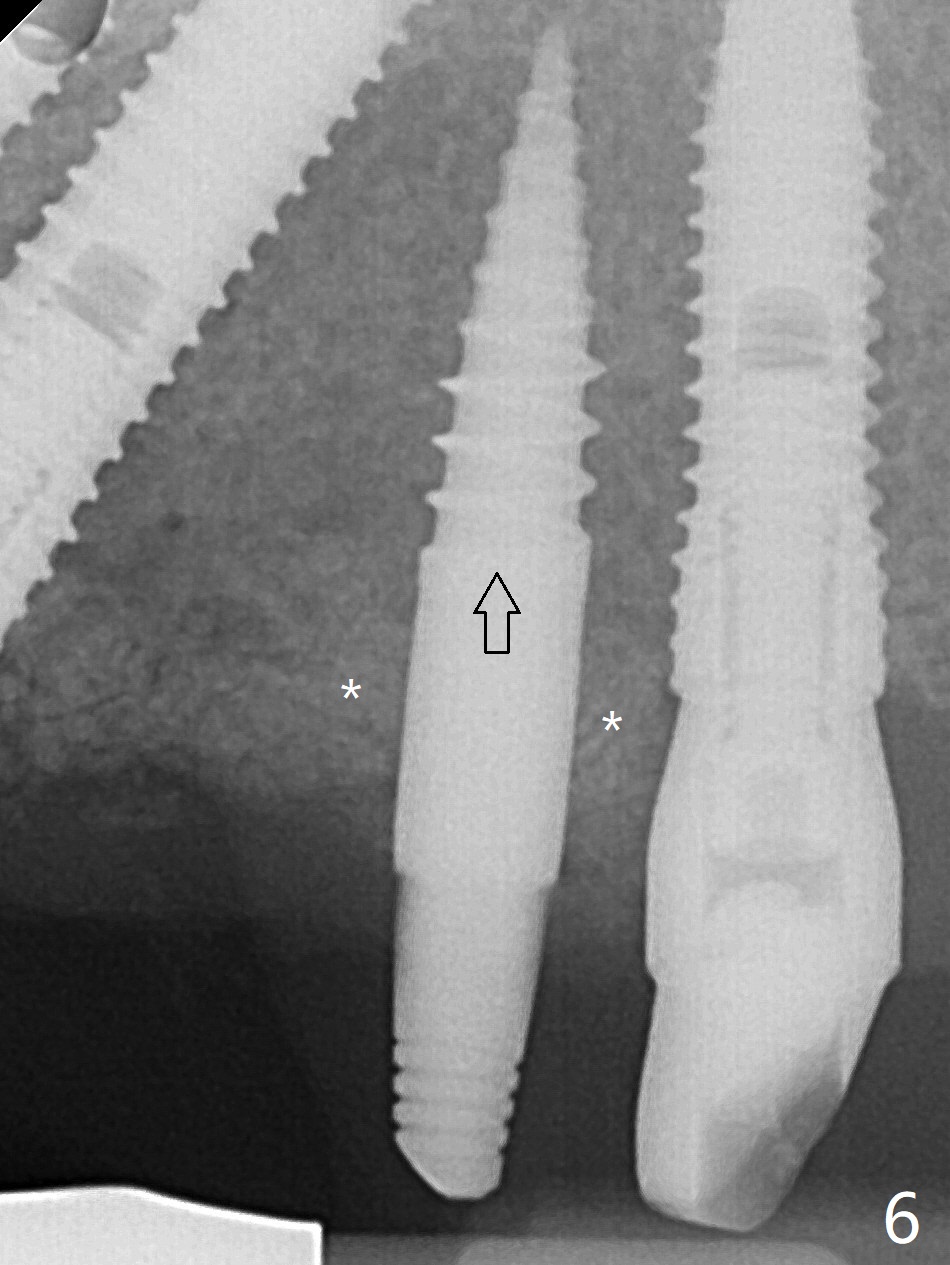

A 48-year-old man returns to clinic with fractured FPD 1 year 5 months post cementation (temp bond, Fig.1,7). It appears necessary to add an implant at #13 site (Fig.2). The narrow ridge is reduced to start an osteotomy (Fig.3 *). After change in osteotomy position and trajectory (Fig.4), a 3x10(4) mm 1-piece implant is placed (Fig.5). With deeper placement of the implant (Fig.6 arrow), cortical bone graft is placed (*).